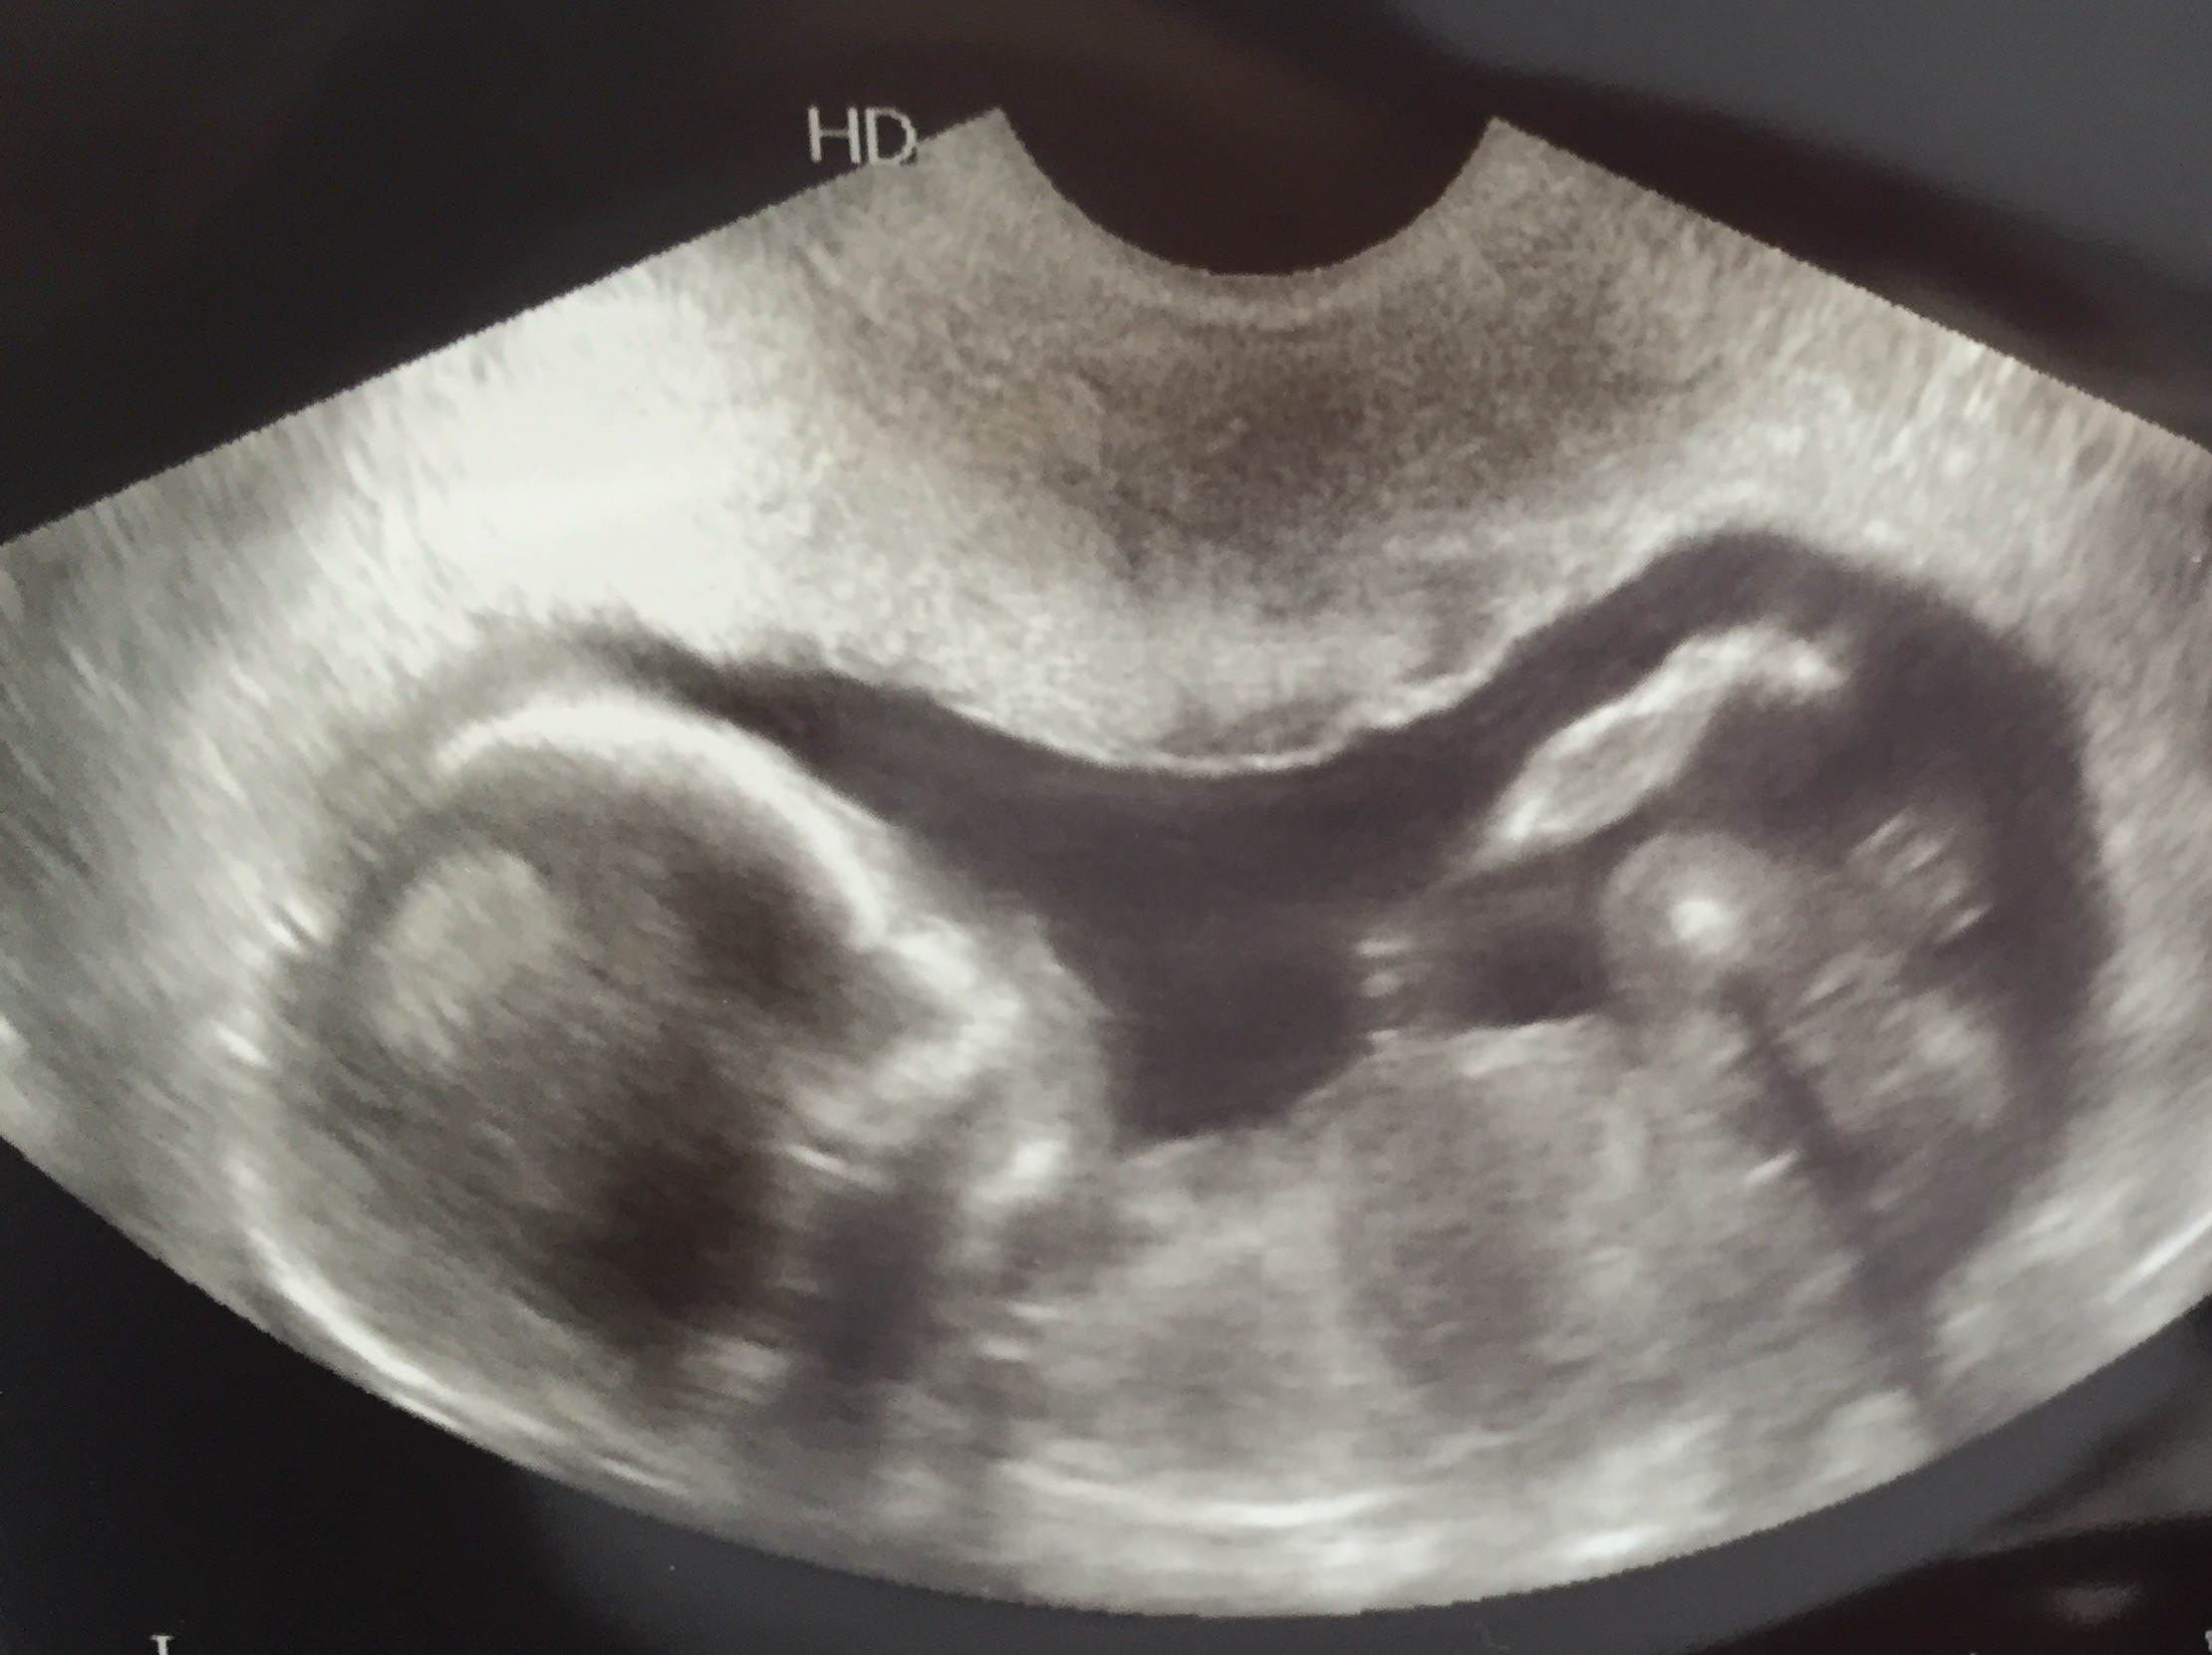

Moj synek

Ogólnie luz, noga na nogę przez całe badanie, machanie łapka i w końcu noga na nogę plus ręce za głowę

. Niesamowite jest to, że takie maleństwo już tak dobrze widać. Kocham i mam nadzieję, że bedzie dobrze do końca. Jestem po 3 stratach, ale do 9 tc.

Moj synek.

Ogólnie luz, noga na nogę przez całe badanie, machanie łapka i w końcu noga na nogę plus ręce za głowę. Niesamowite jest to, że takie maleństwo już tak dobrze widać. Kocham i mam nadzieję, że bedzie dobrze do końca. Jestem po 3 stratach, ale do 9 tc.

Jak pięknie się pokazał.